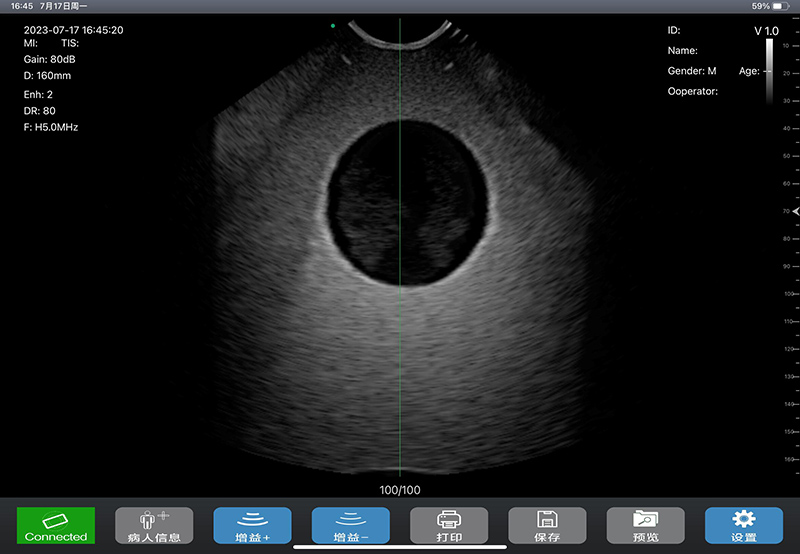

- 先进的计测算法、强大的膀胱壁识别技术、准确的勾边技术,以及高精确度的探头,使得扫查计测结果准确度更高:其中全新算法,计测结果不受膀胱形状、大小影响,使用时无需考虑和选择性别、年龄段,也无需考虑子宫切除等特殊情况对膀胱形状的影响,对不同膀胱兼容性更好,不会发生检测小容积膀胱、特殊形状膀胱时计测结果误差很大的现象,且使用操作也更加方便;而采用AI等技术,对膀胱壁识别更加准确,包括对附着有空气的膀胱壁识别率也比较高,即使膀胱未蓄满尿液时,也能准确计测出尿量,另外AI功能还可对膀胱壁有特异不好勾边的,把异常图拿到训练集里训练,即可解决勾边困难问题

- 扫描过程中图像实时性好,能更好的用于导尿管插拔的实时可视化监测,更好防止盲插给病人带来的痛苦